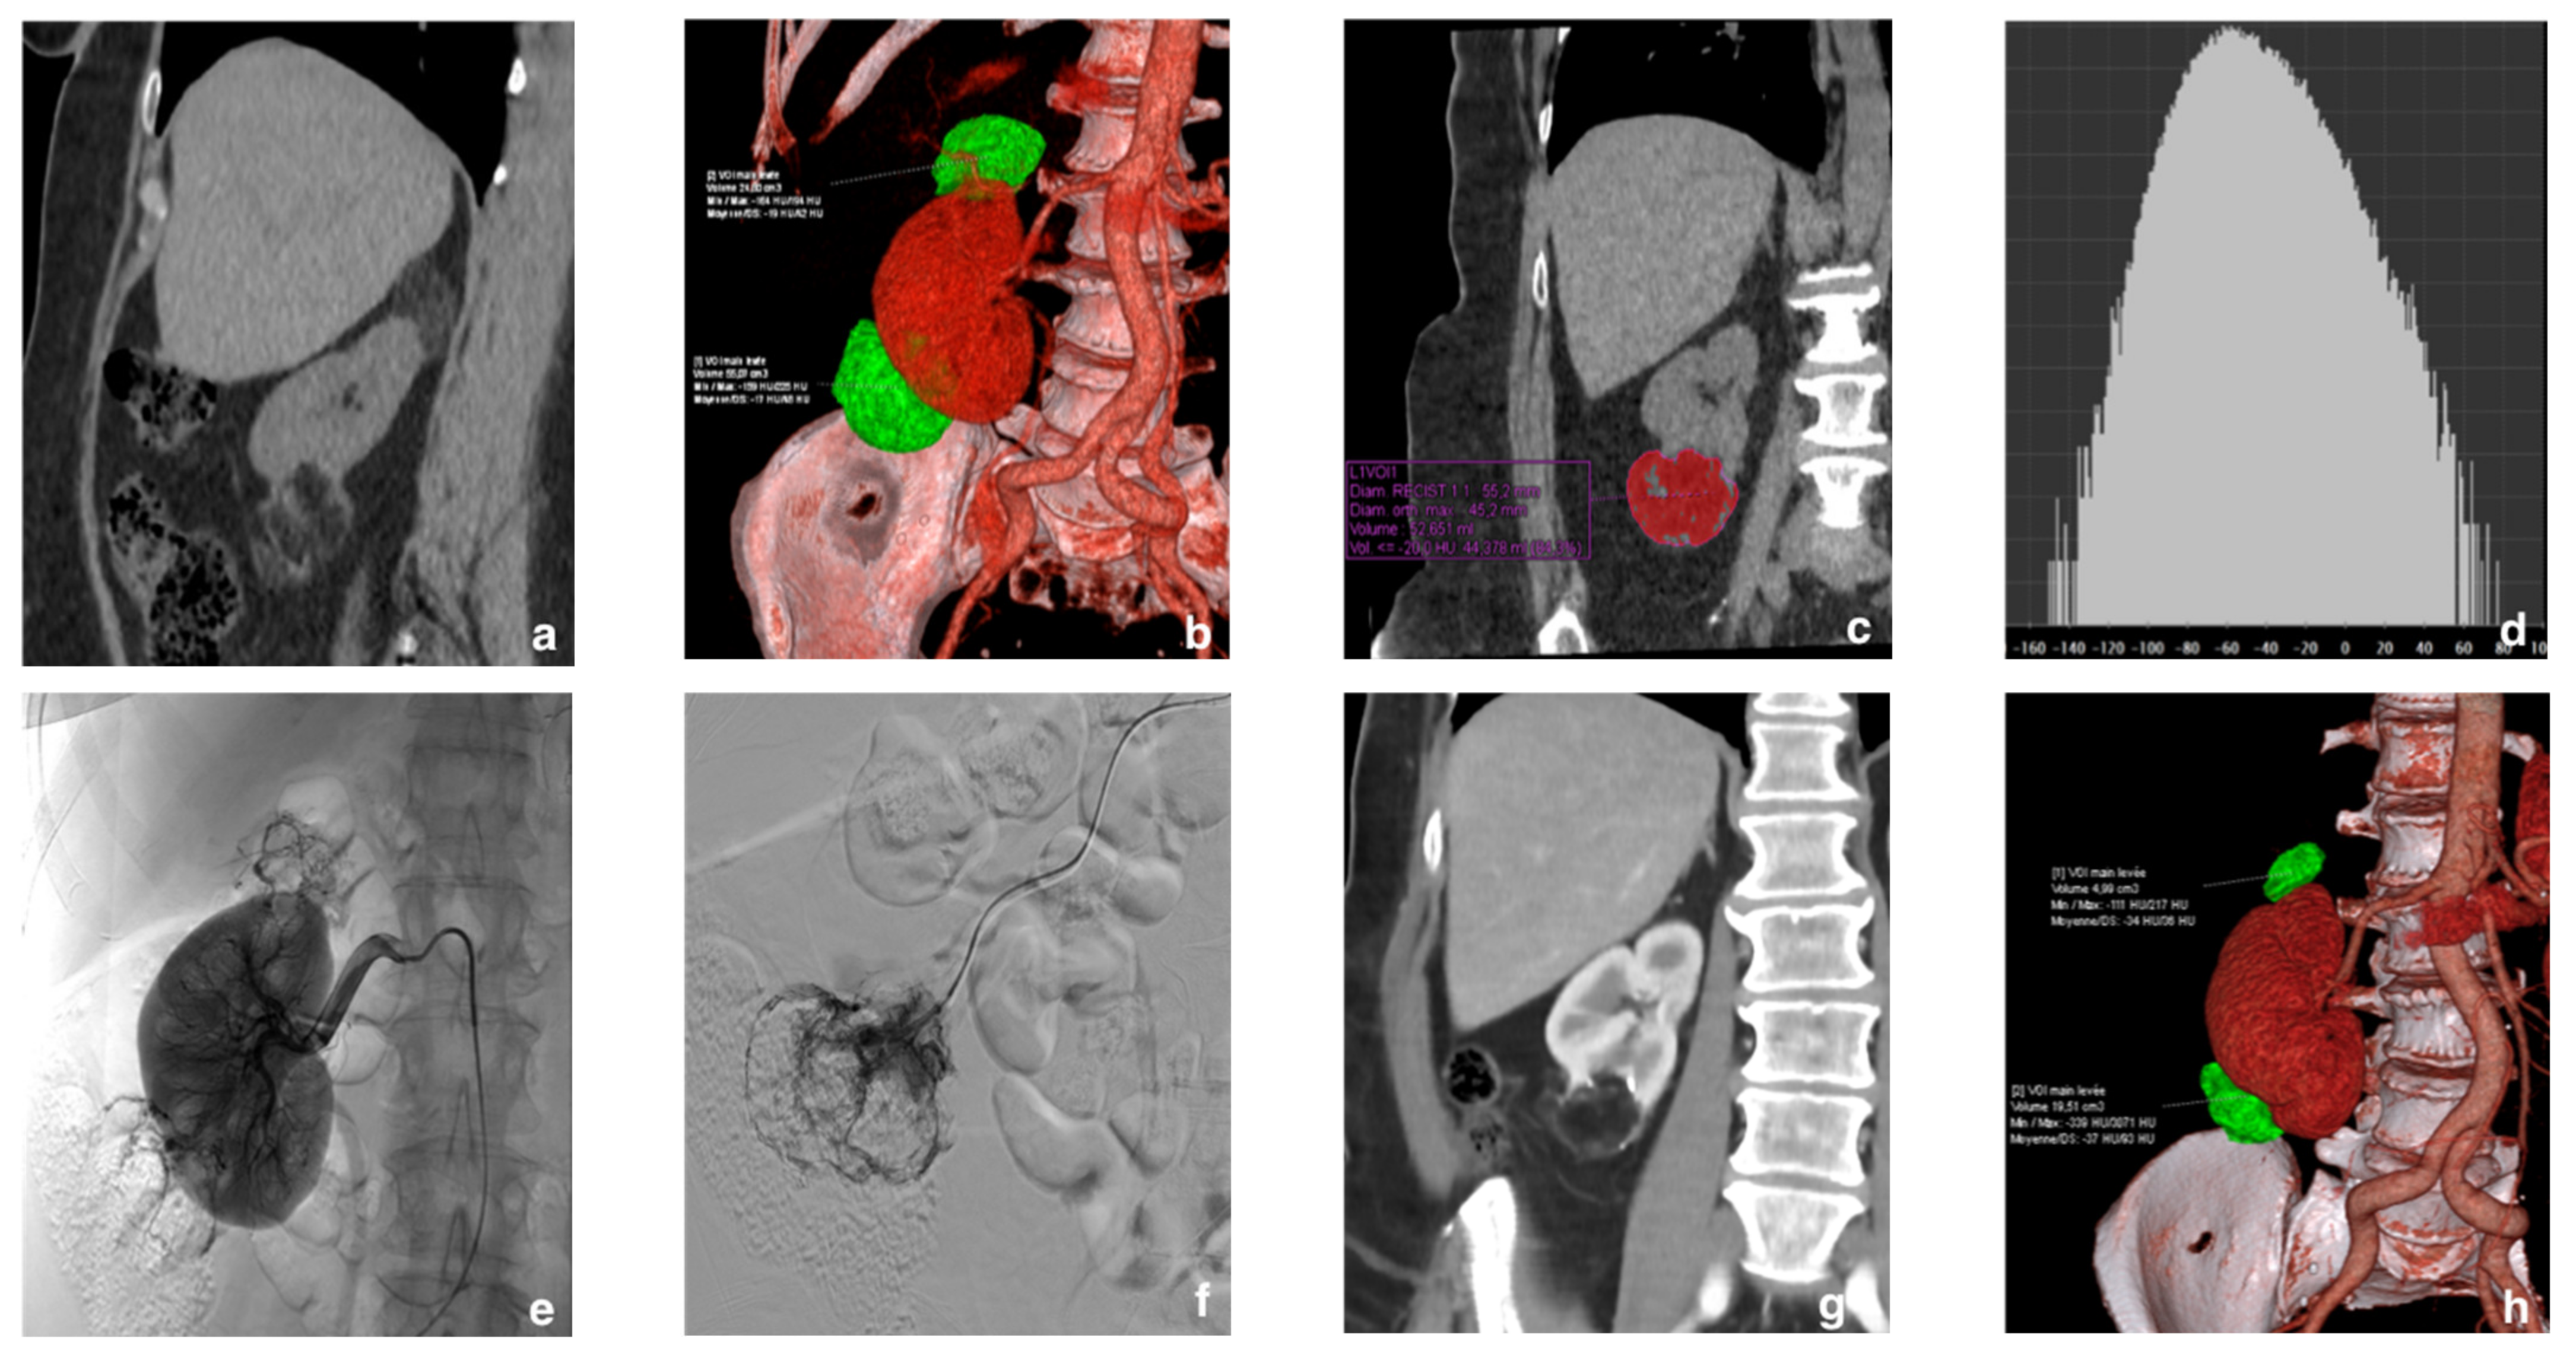

2.2. Diagnosis and Tumor Size

2.3. Selective Arterial Embolization (SAE)

2.4. Follow-Up